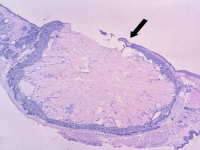

王功伟老师肾脏肿瘤系列讲座(十五):

王功伟

北京大学人民医院病理科